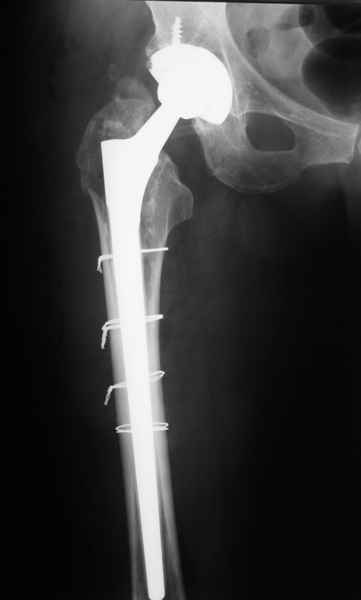

2. Применение ножки дистальной фиксации, мы отдаем предпочтение ножке Вагнера с фиксацией проксимального отдела на ножке. Более травматичное вмешательство, но при стабильной фиксации ножки реабилитация идет в обычном режиме.

Хочется показать два подобных случая, П-ка З. 72 лет и п-т Г. 80 лет. Сразу принимаю замечание, что это были ножки цементной фиксации, просто под руками не было бесцементника.